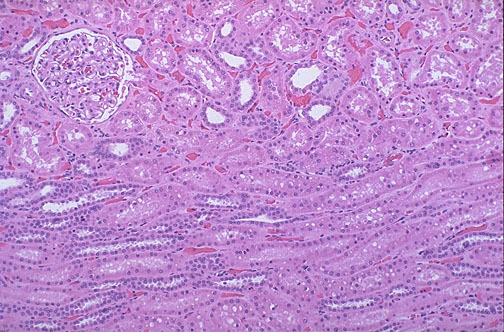

A normal glomerulus at medium power is in the cortex, adjacent to a column of collecting tubules that extend in medullary rays down to a renal papilla interfacing with a calyx.